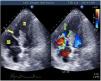

Mujer de 67 años en shock cardiogénico tras infarto de miocardio, con un seudoaneurisma y comunicación interventriculares (CIV): disposición oblicua, medial-anteroseptal a septoapical (fig. 1). Tras la estabilización, se repara con parche bovino. En controles ecocardiográficos objetivamos disfunción del ventrículo derecho (VD) y persistencia de la CIV: con escaso relleno diastólico del seudoaneurisma desde el VD y un predominante relleno sistólico turbulento desde el ventrículo izquierdo (VI), que evacúa al VD mediante 2 jets (Video 1). El salino agitado confirma un discreto relleno del seudoaneurisma desde el VD y rápido lavado del mismo desde el VI, así como el paso de algunas burbujas desde el VD al VI (fig. 2, Video 2). La grave disfunción derecha imposibilitó nueva reparación. Flechas amarilla: seudoaneurisma; flecha verde: CIV; flecha azul: burbujas en el VI; flecha roja: parche. Planos ecográficos: apical 4/5 cámaras y modificado.